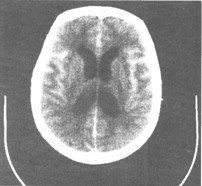

脊髓蛛網膜軟脊膜之間有一寬大的間隙,名叫蛛網膜下腔,腰部最大,內含腦脊液

蛛網膜下腔穿刺經:皮膚-皮下-棘上韌帶-棘間韌帶-黃韌帶-硬膜外腔-硬脊膜-蛛網膜-蛛網膜下腔。

蛛網膜下腔下緣:蛛網膜下隙的下部,自脊髓下端馬尾神經根部至第二骶椎水平擴大的馬尾神經周圍的蛛網膜下隙,稱終池,內容馬尾。